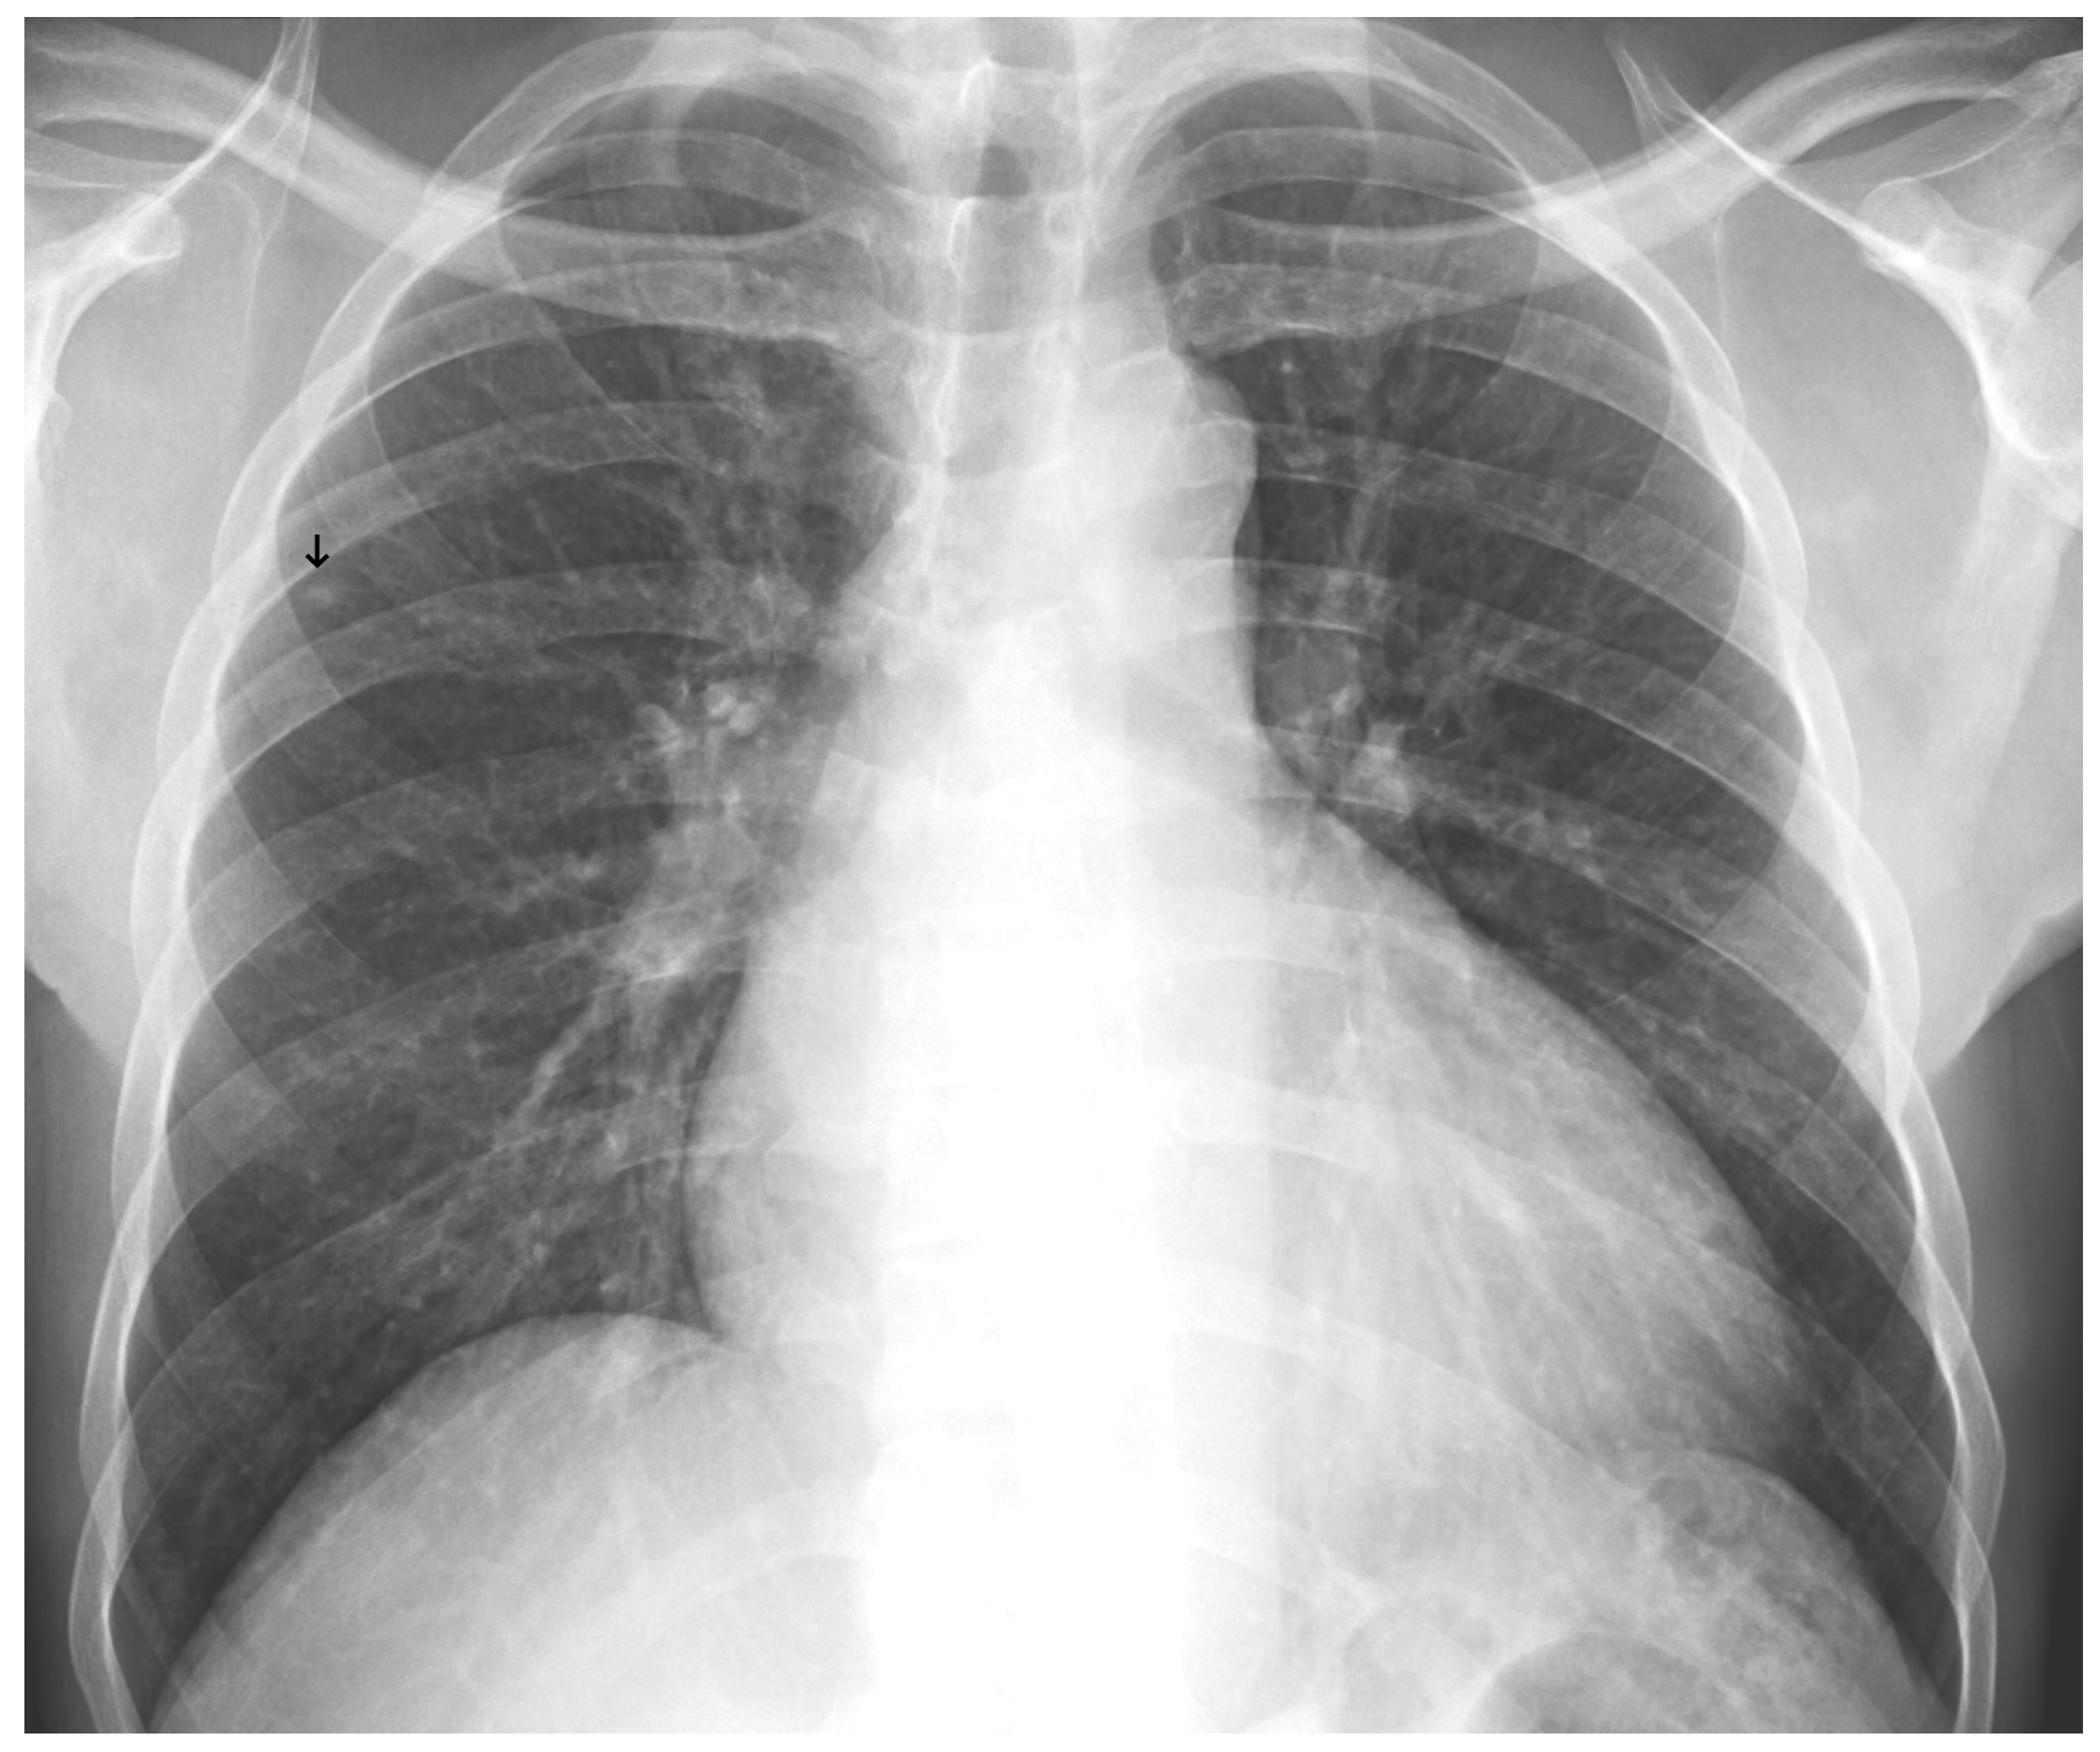

An analysis of the algorithm’s false negatives revealed a nuanced performance profile, where a specific miss did not always equate to a complete system failure. Across the board, a substantial number of cases with a false negative for a particular pathology were nevertheless correctly identified as abnormal by the general “yes-finding” classifier or had other co-occurring true positive pathologies. For example, out of 38 false negatives for opacity, the algorithm correctly identified the exam as abnormal in 25 cases. In many instances of a missed finding, the algorithm successfully detected other pathologies within the same study. Misclassification was another notable source of error, where an existing pathology was detected but incorrectly labeled, such as opacities being predicted as masses or nodules (Figure 4). Radiologist review of these false-negative cases frequently noted findings that were “subtle,” “small,” “doubtful,” “seen on lateral image only,” or “non-specific.” In other cases, the algorithm correctly identified a more critical finding, like a large pleural effusion, while missing a secondary, less significant pathology (Figure 3). Figure 9, Figure 10 and Figure 11 illustrate false negative cases for opacity, pneumothorax, and nodule, respectively. This highlights the inherent limitations and inevitable failures of this kind of system.

Figure 11. A false negative example of a missed loculated pneumothorax. The presence of pulmonary markings (black arrow) beyond the pleural line (white arrowhead) may have misled the algorithm.